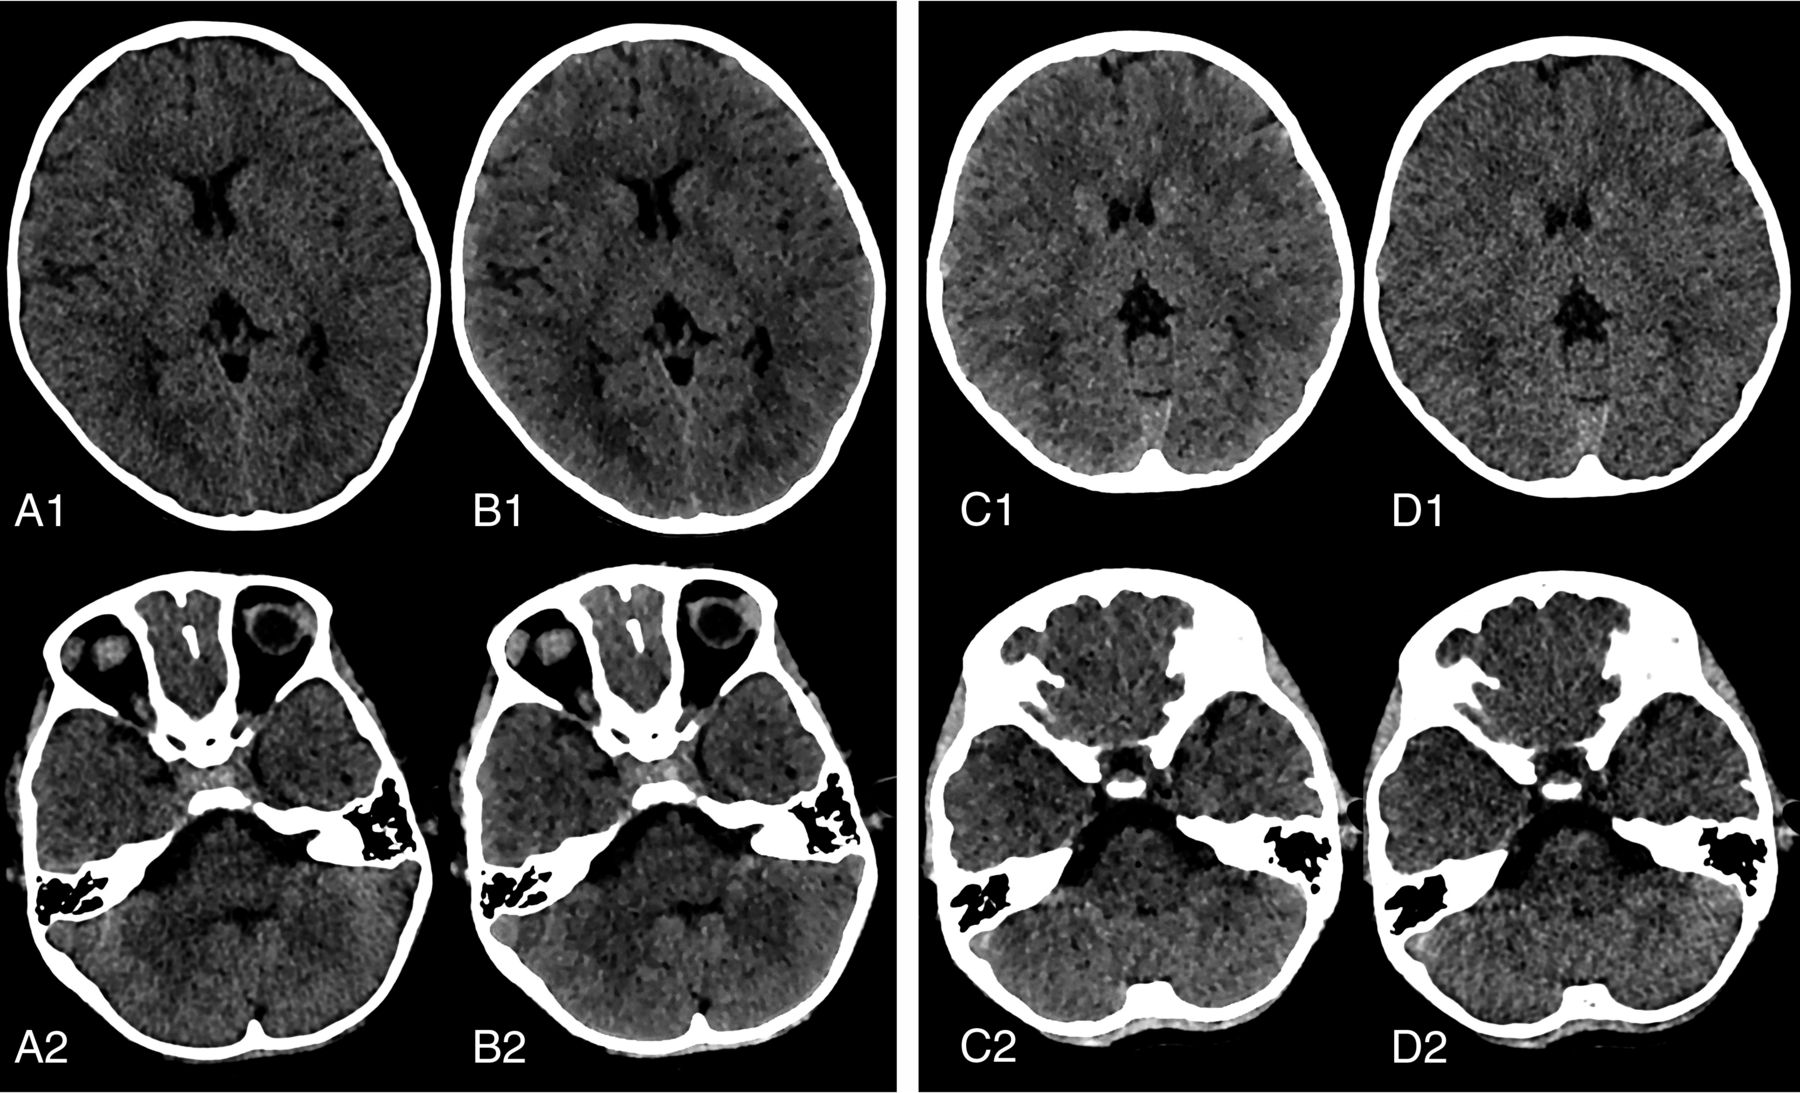

Representative images showing improved image quality in the supratentorial and infratentorial brain parenchyma for conventional images and 60-keV VMIs acquired using 250 and 180 mAs. Axial reconstruction conventional image (A) and 60-keV VMI (B) for nonenhanced brain CT scans acquired with 250 mAs in a 6-year-old girl with neuroblastoma in the retroperitoneal area. Axial reconstruction conventional image (D) and 60-keV VMI (C) for a nonenhanced brain CT scan acquired with 180 mAs in a 6-year-old girl with exotropia in the eye. GWMA (B1, C1), SSA, and PFAA (B2, C2) and overall image quality were better for 60-keV VMIs compared with conventional images (A1, D1, A2, and D2), respectively. Subjective image-quality indices were similar in 60-keV VMIs between the 250-mAs (B1, B2) and 180-mAs (C1, C2) groups. Window settings were kept identical for better comparability (level, 35; width, 70).